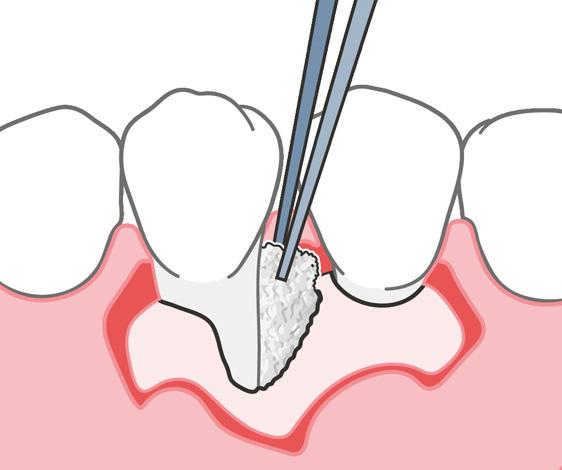

Injertar el defecto con un sustituto óseo y cubrirlo con una membrana reabsorbi ble puede ayudar al organismo a corregir

el defecto. En los tratamientos endodón ticos regenerativos para defectos gran des, como con la terapia periodontal regenerativa, los dentistas usan hueso autógeno y biomateriales, o una mezcla de ambos.

Microcirugía periapical regene rativa

La microcirugía periapical regenerativa emplea los principios fundamentales de la endodoncia, la periodoncia y la odonto logía oral y restauradora. Por lo general, el objetivo del tratamiento es eliminar todos los posibles factores causantes de lesio nes periapicales, reparar la arquitectura del tejido periapical perdido y conservar la estructura y la anatomía de la raíz y de los tejidos blandos. También es importan te prevenir la recidiva de la enfermedad a largo plazo.

Los índices del éxito de la microcirugía periapical regenerativa han aumentado de manera notable en los últimos años gracias a los avances en las técnicas di gitales para la planificación, la microsco pía, los instrumentos microquirúrgicos y los biomateriales para la regeneración ti sular guiada.3 4

La selección de los materiales regenerativos

A pesar de que los injertos autógenos sue len considerarse como el método de re ferencia para la odontología regenerativa, no siempre son la mejor opción. Suelen estar asociados a un dolor y una morbili dad mayores, porque es necesario extraer el injerto. En una revisión sistemática, Chavda y Levin (2018) constataron que los pacientes preferían sustitutos óseos no autógenos, porque se reducían los días de la hospitalización, el dolor era menor y el tiempo de recuperación era más cor to.5 Los autores no observaron ninguna

diferencia en el índice de éxito de los im plantes cuando la cresta alveolar se au mentaba con diferentes injertos óseos, in cluido el hueso autógeno.5

Uso biomateriales para las microcirugías periapicales y, hasta la fecha, estoy muy satisfecho con los resultados clínicos. El protocolo me ha permitido ayudar a mu chos pacientes a conservar sus dientes naturales insalvables, y a mantenerlos sanos y funcionales. Recientemente, mis colegas y yo publicamos un caso clínico donde detallábamos el protocolo y el re sultado clínico en el manejo de una lesión radicular grande mediante microcirugía periapical regenerativa.3 El quiste medía 40 mm en la zona más grande, y afectaba a varios dientes anteriores, a ambas placas corticales y en parte al suelo nasal. Debi do a las grandes dimensiones del defecto, decidimos usar una mezcla de Geistlich Bio‑Oss® y hueso autógeno obtenido de la rama ascendente de la mandíbula, junto con fibrina rica en plaquetas. El resulta do clínico era satisfactorio 4 años después de la cirugía (es decir, en el momento de la publicación). Además, cuando estudia mos las imágenes de la tomografía com putarizada de haz cónico, observamos que los tejidos estaban bien integrados, había hueso cortical nuevo y una radio pacidad y una forma trabecular parecidas a las del hueso nativo adyacente.